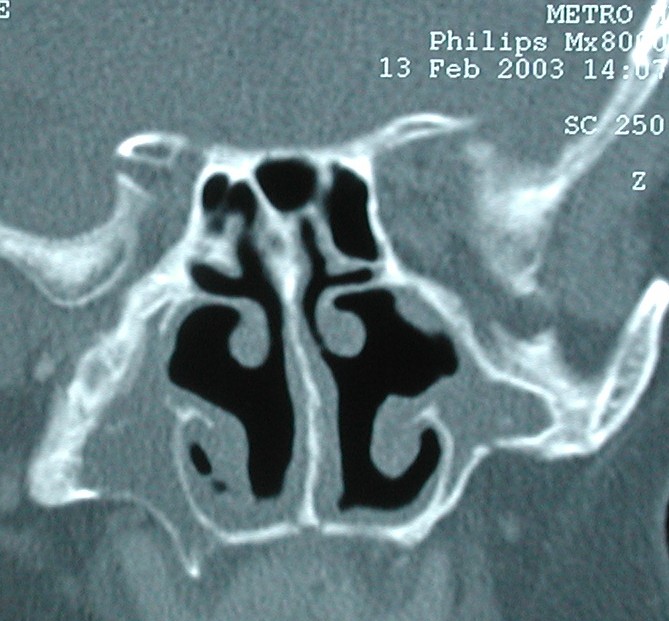

This CT depicts a fascinating finding: the patient has a concha bullosa of the left inferior turbinate.  Furthermore, the IT air pocket connects to her maxiallry sinus.  Also (not shown) the nasolacrimal duct drained into the maxillary sinus rather than the nose.  They presented with nasal obstruction: a turbinate outfracture was performed AFTER the air cell was opened into the inferior meatus.